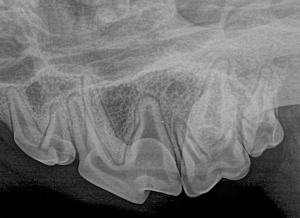

Feline Full Mouth Radiograph example